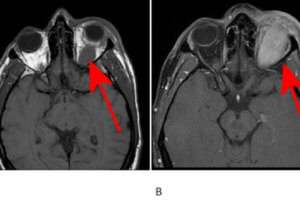

Orbital Pseudotumor

Orbital pseudotumor is the most common cause of a painful orbital mass in adults. It is a mass comprised of inflammatory cells (lymphocytes, macrophages etc) and fibrosis, is typically unilateral and infiltrative. Read more »